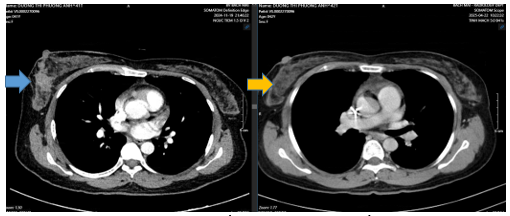

- CT ngực trước và sau điều trị tân bổ trợ

Hình 4: Vú phải vị trí 1/2 dưới , có khối ~50x34mm (Trước điều trị mũi tên xanh). Sau điều trị giảm còn ~ 24x17 mm (Sau điều trị mũi tên vàng)

Như vậy sau 6 chu kì điều trị tân bổ trợ phác đồ TCHP cho thấy bệnh đáp ứng một phần, u và hạch giảm đáng kể kích thước. Bệnh nhân được chỉ định cắt toàn bộ tuyến vú phải và vét hạch nách (5/2025)